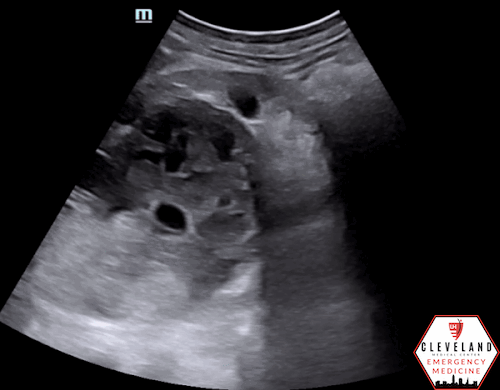

Sagittal view of the right upper quadrant with a large complex mass seen extending from the superior pole of the kidney

POCUS findings: In the right upper quadrant, a large complex cystic structure was seen extending from the superior pole of the right kidney. It has mixed echogenicity with hypoechoic areas suggestive of fluid. It appears contained and no free fluid is seen. Color doppler shows no evidence of internal flow. His other kidney was normal-appearing and his bladder was decompressed.

Case Continued: CT was read as a large (9 x 9 x 8 cm) complex, mostly cystic mass in the right kidney with thickened walls with nodularity and internal debris with infiltration into the perinephric fat along with fluid. This was concerning for a complex mass versus hematoma in the setting of trauma. Ultimately, radiology and urology felt that this was most likely a rare cystic renal cell carcinoma. He was admitted for pain control, physical and occupational therapy, and facilitation of further workup.

Cystic renal cell carcinoma (CRCC), a rare form of RCC as seen in this case, often appears sonographically as a hypoechoic mass with hyperechoic septa, thick capsule walls, and possible nodules attached to the septa. It is rare but not impossible for CRCC to have a unilocular appearance, potentially causing diagnostic delay as it can mimic benign simple cysts. Nephrectomy is the treatment of choice for CRCC with most data supporting nephron-sparing surgery (5). The prognosis is reassuring, with the 10-year survival rate and non-recurrence rates of 97.3% and 90.3% (12).